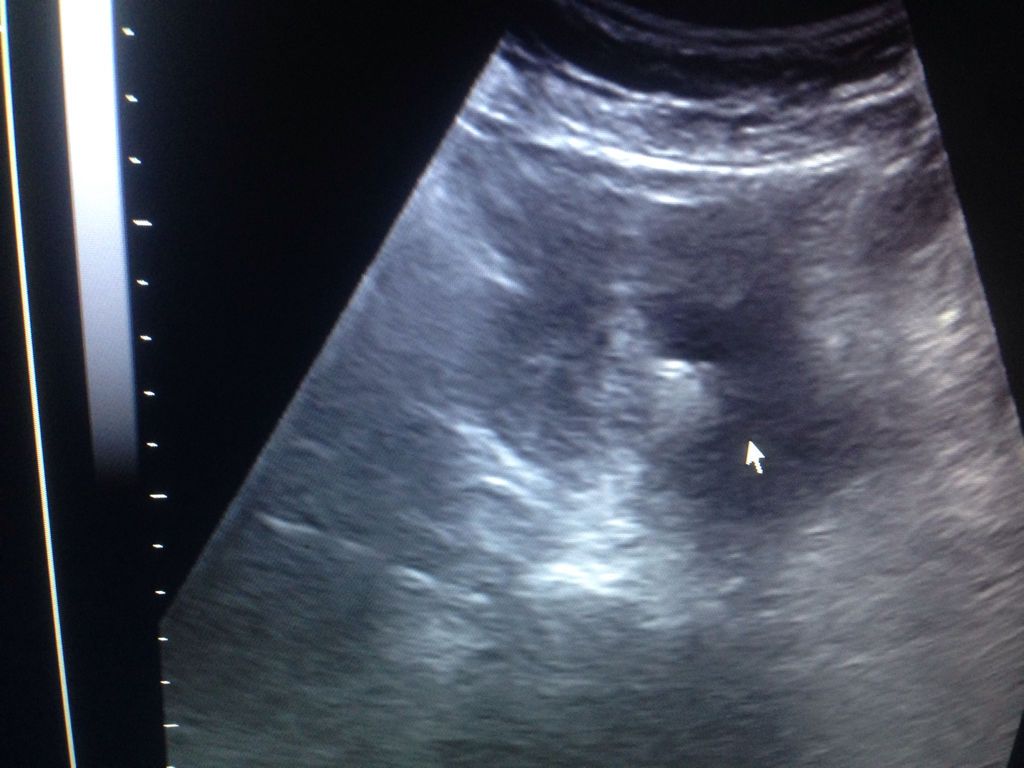

这算是怀孕吗?在中医院检查说是怀孕,从专业从事妇产科的医院检查都说怀孕「检查血液怀孕」也有做阴超也 这算是怀孕吗?在中医院检查说是怀孕,从专业从事妇产科的医院检查都说怀孕「检查血液怀孕」也有做阴超也说怀孕。今天去检查B超说是死胎?怎么回事?请专业人士回答! 点击展开 匿名用户 2016-04-30 13:51 为您推荐: 其他回答 建议你截图超声检查我看一下。 东郭灵慧_eGp2 2016-04-30 13:53 还是找专业医生给你看吧,不要自己乱猜 woyuying2 2016-04-30 13:53 无胎心胎芽 匿名用户 2016-04-30 13:51 相关问题 老婆孕期18周+五天,由于有阴道炎,上午去妇产科医院检查,检查后中午阴道出血,下午又回去做B超检查 我怀孕6周,今天早上和丈夫同床,然后出血了,去医院检查,做了彩超没发现,又做了阴超还是没发现,现在 第一次怀孕,用试孕纸试的时候是怀孕的,但去医院照B超看不出,然后过几天又去做了阴B超,医生说是先兆